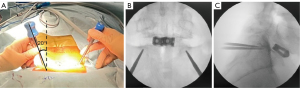

Initially, TLIF at L5-S1 was conducted using two cages, accessed either through a 4-cm longitudinal median incision or the Wiltse approach via a paramedian incision. Under fluoroscopic guidance, it is crucial to align the tilt of the S1 endplate with the fluoroscopic angle in the anteroposterior view. The entry point for S1 was located 1.5 cm caudal to the edge of the S1 upper endplate and 1.5 cm lateral to the medial border of the S1 pedicle, which is typically located in the lateral wall of L5 (Figure 2). The PSEPS trajectory was angled 20° inward toward the anterior third of the S1 endplate. A conventional straight probe was inserted and directed cephalad until it reached the cranial margin of the S1 end plate (Figure 3A,3B). The placement of the probe beyond the posterior wall of the vertebral body was confirmed in the lateral view (Figure 3C). The M-probe was replaced with a guidewire, and the guidewire was replaced with a cannula before advancing the M-probe toward the anterior third of the S1 vertebral endplate using a hummer. The cephalocaudal orientation of the trajectory was adjusted by rotating the tip of the M-probe by 180° (Figure 4A-4C). When the tip arrived at the S1 endplate, the M-probe was oriented cephalad and advanced forward to penetrate the endplate (Figure 4D-4F). Rotating the tip of the M-probe enlarges the bone hole in the S1 endplate and eliminates the need for tapping. Finally, a guidewire was used to verify the position of the tip in the intervertebral disc, followed by the insertion of the S1 PSs. The L5 PSs was placed using a conventional straight probe. Intraoperative C-arm images demonstrated the optimal positioning of the S1 screw (Figure 5). Precept spinal system screws (NUVASIVE) was used for all patients.

The PSEPS trajectory was angled 20 °inward toward the anterior third of the S1 endplate, whereas the EPS trajectory moved straight toward the center of the S1 endplate (Figure 6). The PSEPS trajectory has several advantages: (I) the inward trajectory decreases the risk of neurovascular injury; (II) the guidewire can be safely placed within the intervertebral disc; and (III) longer screws can be used for increased stabilization. Due to the thickness and hardness of the sacral endplate, patients with a small sacral slope are more prone to anterior slippage when a straight probe is used to penetrate the endplate. This indicates an increased likelihood of anterior slippage when using a straight probe, potentially resulting in unintended bicortical or tricortical purchases. Orienting the curvature of the M-probe toward the S1 endplate made it easier to angle the approach relative to the S1 endplate. Additionally, a shape-memory alloy (Nitinol) guidewire was used to reduce the risk of guidewire breakage when a curved hollow probe was used.